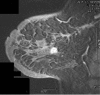

In the last decade,there have been huge advances in the field of breast imaging.Full field digital mammography systems optimise lesion to background contrast with resultant improvement in the sensitivity of the technique for cancer detection, facilitated by computer-aided detection.Though mammography remains the only established modality for population-based screening, preliminary results from several large studies indicate that magnetic resonance imaging(MRI) has a role in high-risk patients.On the other hand, advances in ultrasound, MRI and nuclear medicine have the potential to greatly improve the specificity of breast imaging with regard to cancer detection and lesion characterisation.A number of new and experimental techniques are being developed which may have great impact in this area and these will be discussed. Though MRI now has an established place in the diagnosis of breast cancer, it is becoming clear that it can directly affect surgical and medical management by enabling assessment of response to chemotherapy and endocrine therapy, and facilitating choice of the most appropriate surgery.Just as the role of MRI has evolved,so too the place of nuclear medicine, particularly positron emission tomography and radio-immunoscintigraphy should become clearer in the next few years.